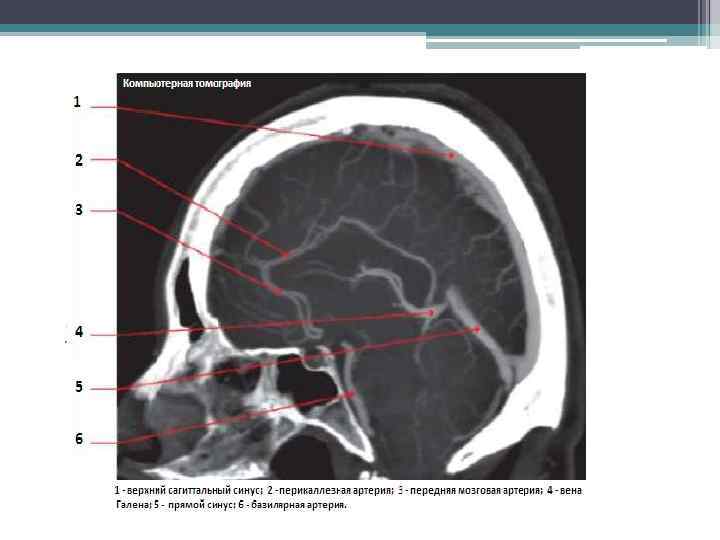

Диагностика: АВМ головного мозга проявляются характерными признаками по данным МРТ характеризуется высокой чувствительностью в выявлении АВМ, при этом может иметь место пустотный сигнал в Т 1 и Т 2 режимах, часто со следами гемосидерина. КТ обладает низкой чувствительностью в выявлении АВМ, однако КТ -ангиография высоко информативна. Ангиография является золотым стандартом в выявлении артериальной и венозной анатомии АВМ. При АВМ головного мозга специфичных изменений лабораторных показателей нет.